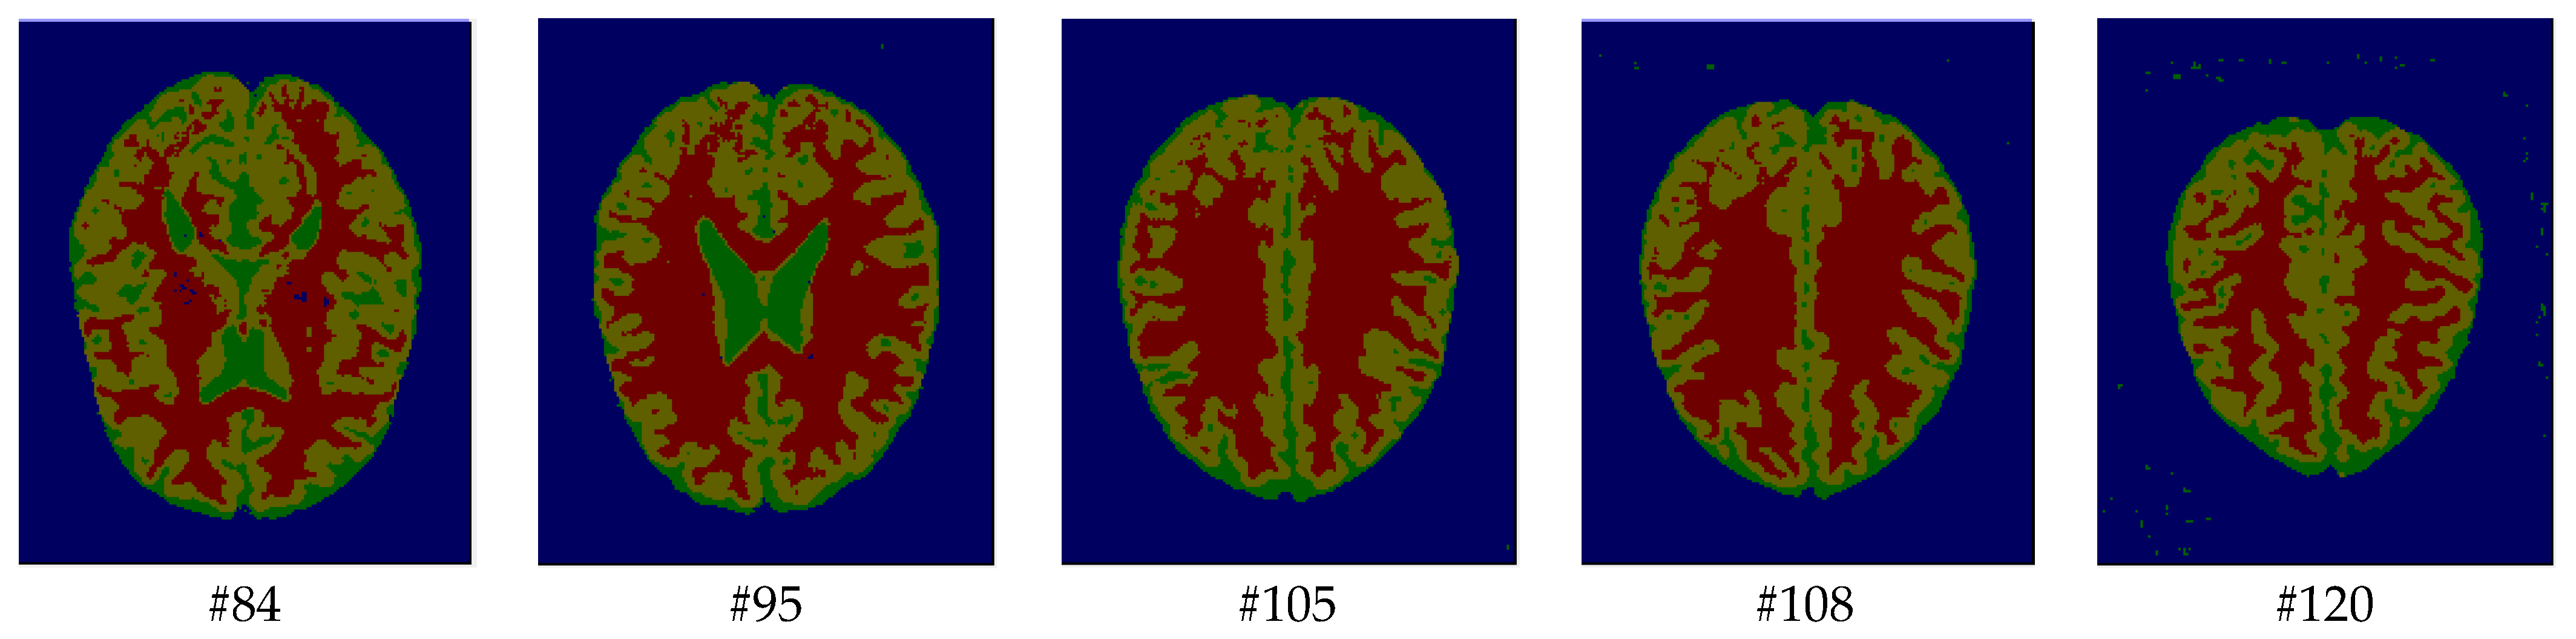

As mentioned before, the images of the first five datasets in Table 3 were used to evaluate the performance of the HMRF-WOA. Figure 1, Figure 2, Figure 3, Figure 4 and Figure 5 show some slices of a T1-weighted image (slices: 84, 95, 105, 108, 120). These brain images correspond to the slices under different types of conditions, such as database type, dimension image, noise level, intensity non-uniformity level, and slice thickness (mm). In Table 1, rows 1 to 5 summarize the parameters of Figure 1, Figure 2, Figure 3, Figure 4 and Figure 5, respectively. Figure 6 represents the ground truth segmentation of slices 84, 95, 105, 108, and 120. In this figure, each column contains the three tissues, GM, WM, and CSF, of each slice. Figure 7, Figure 8, Figure 9, Figure 10 and Figure 11 show the segmentation results, where the four tissues (BG, GM, WM, and CSF) are shown with different colors. The yellow, red, and green colors represent the segmented regions of GM, WM, and CSF, respectively. As we can also see from these figures, the resulting segmented images in Figure 7, Figure 8, Figure 9, Figure 10 and Figure 11 are almost close to the initial images in Figure 1, Figure 2, Figure 3, Figure 4 and Figure 5.

The qualitative analysis provides a visual representation of the segmentation approaches. The visual comparison of the resulting images using the HMRF-WOA appears to be more similar to the reference image (ground truth), where Figure 1, Figure 2, Figure 3, Figure 4 and Figure 5 show the GM, WM, and CSF tissue regions of the reference image with higher values of noise levels (3, 5, 7, and 9%) and intensity non-uniformity levels (20, 40%), whereas Figure 7, Figure 8, Figure 9, Figure 10 and Figure 11 show the subject images obtained using the proposed technique. However, this result shows that with higher values of noise and intensity non-uniformity, the algorithm, with its hyperparameters, is able to segment the tissue regions correctly.

Figure 7. Segmentation results of the slices illustrated in Figure 1.

Computers 13 00124 g007